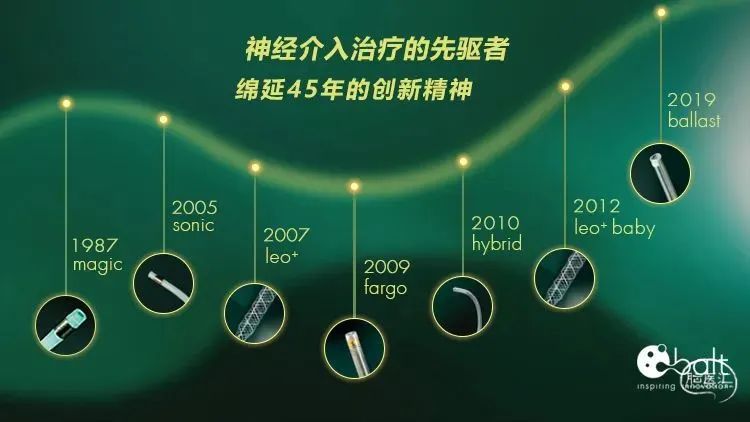

遂选择具有优异血管顺应性的编织型支架,植入后能够保留治疗通路,未来远端血管发生病变时仍能够通过介入方式进行治疗,同时高金属覆盖率有利于瘤颈修复,还能避免使用小圈栓塞小分叶瘤体时跑圈。

LEO+Baby支架 2.5*18mm 、2.5*12mm